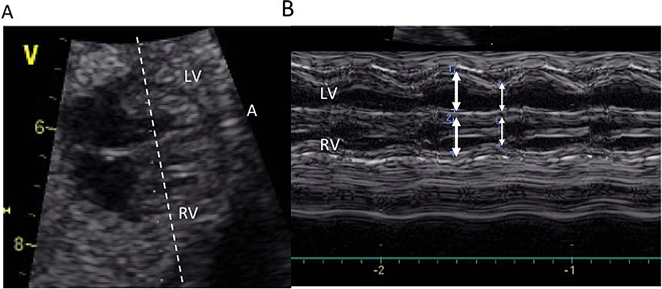

右心室と左心室両方の収縮率を用いて各心室の収縮能を評価する.四腔断面において中隔に対しにほぼ垂直,長軸方向房室弁直下の位置になるようにかつカーソルの位置を設定する.この時Mモードの記録には僧房弁,三尖弁動きも同時に記録されるため収縮期,拡張期を決めやすい(Fig. 2).Mモードの記録から心室内腔の拡張末期径と収縮末期径の差を拡張末期径で除することで算出される.正常値は週数によらず一定で0.28~0.401).また胎児の位置から前述のような評価が困難な場合には,心室内腔をトレースしmodified Simpson法で収縮率を求める方法もある2).いずれの方法も,胎児という特殊性による測定誤差を考慮して判断する必要がある.

Fig. 2 Measurement of the shortening fraction

A: A four-chamber view of the fetal heart. The cursor was set perpendicular to the ventricular septum. B: M-mode of Figure2-A. Without an electrocardiogram, measurement is done at the widest dimension as diastolic one (thick arrows), and the shortest dimension as systole (arrows). (A: anterior, LV: left ventricle, RV: right ventricle)